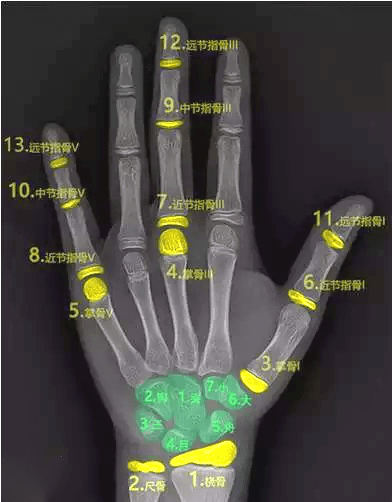

三、骨齡測試法

骨齡是骨骼年齡的簡稱,比實際年齡更能反映人體骨骼的成熟度。

一般是拍攝左手腕部的X線片,觀察指骨、腕骨、橈骨、尺骨下端的骨化中心出現(xiàn)的時間、面積大小、判斷骨骼實際發(fā)育程度,來確定骨齡。

如果骨齡小于生活年齡1歲以上,提示有生長激素缺乏癥的可能;骨齡大于生活年齡1歲以上的孩子可能早熟,往往其成年的最終身高反而受損。

因此骨齡異常需要盡早到專業(yè)醫(yī)療機(jī)構(gòu)就診,必要時進(jìn)行醫(yī)學(xué)干預(yù)和藥物治療。